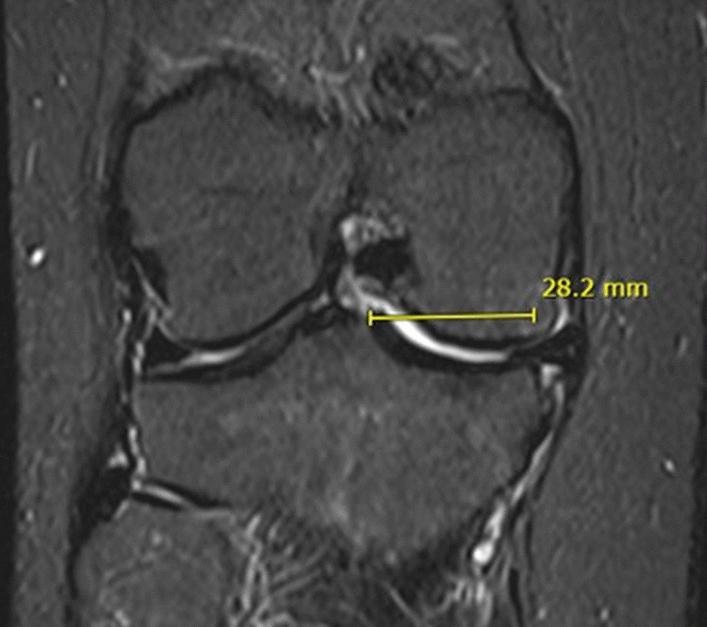

This study's goal is to propose a straightforward classification system based on the MEI (Meniscal Extrusion Index), a measure of meniscal extrusion, that relates to various meniscal lesion patterns and has clinical and biomechanical significance. The study's secondary goal is to determine whether the standard 3 mm meniscal extrusion parameter still has value by correlating the MEI with it.

In the 1350 MRIs that were examined for this study, meniscal extrusion of any grade was present 18.9% of the time. The use of the MEI revealed three groups of patients: those with a MEI < 20%, who are likely para-physiological; those with a MEY between 20% and 40%, who are in a grey area; and those with a MEY > 40%, who have lesions that are impairing the proper meniscal function. According to the authors' findings, the percentage of meniscal extrusion did not correlate with the finite number (3 mm), making the 3 mm parameter an unreliable evaluation method.

本研究旨在提出一种基于半月板挤出指数(MEI)的简单分类系统,该指数与各种半月板病变模式相关,具有临床和生物力学意义。本研究的次要目的是通过将 MEI 与标准 3mm 半月板挤出参数相关联,确定该参数是否仍具有价值。

在本研究中检查的 1350 份 MRI 中,任何等级的半月板挤出的发生率为 18.9%。使用 MEI 显示了三组患者:MEI<20%的患者可能处于生理边缘;MEI 在 20%至 40%之间的患者处于灰色区域;MEI>40%的患者有损伤,会影响半月板的正常功能。根据作者的发现,半月板挤出的百分比与有限的数值(3mm)不相关,这使得 3mm 参数成为一种不可靠的评估方法。